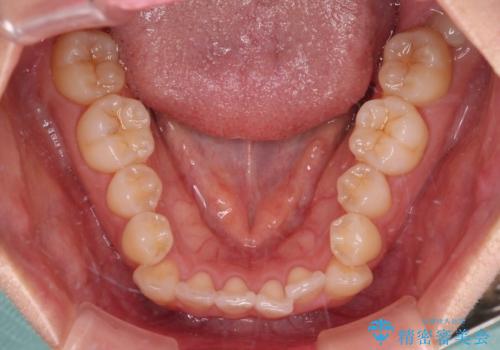

- 上下前歯のデコボコを気にして来院された患者様です。

インビザラインによる上下歯列の拡大と、IPR(歯と歯の間を削る)にるスペースの獲得により、前歯のデコボコを改善することとしました。

下顎前歯は後戻りを起こしやすいため、舌側を細いワイヤーで固定し、マウスピース型リテーナーで保定を行うこととしました。